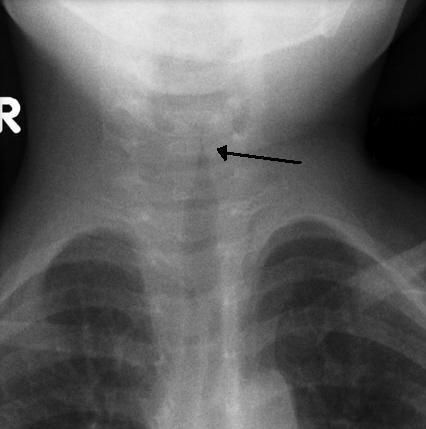

Neck X-Ray AP: Steeple sign

X-ray anteroposterior and lateral neck

Steeple sign